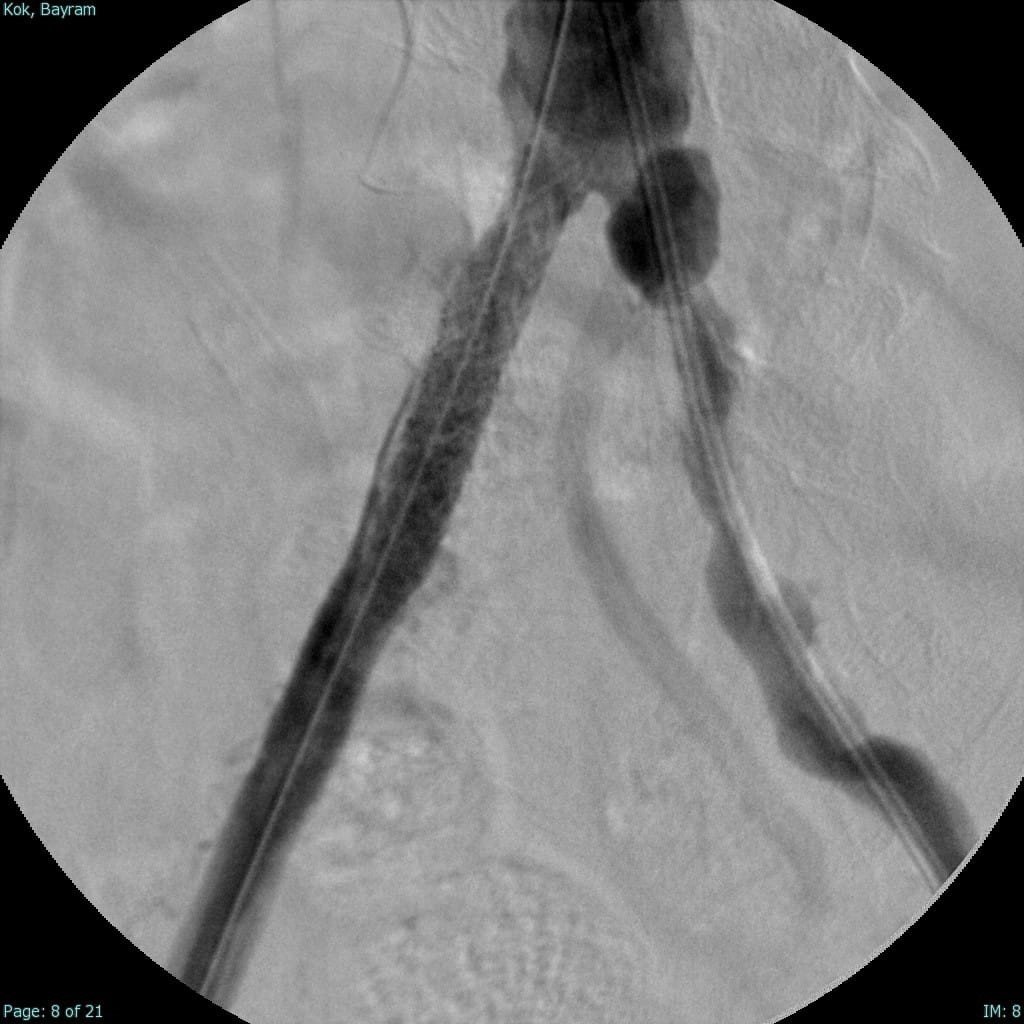

Türkiye'nin ilk yerli stent grefti Bezmiâlem Vakıf Üniversitesi Tıp Fakültesi'nde Prof. Dr. Cengiz Köksal ve Doç. Dr. Emre Selçuk'un öncülüğünde Artven koordinasyonuyla bir hastaya başarıyla uygulandı. Doç. Dr. Emre Selçuk, bu büyük adımı şöyle değerlendirdi:

"Stent-greft teknolojisi, damar tedavilerinde kritik bir rol oynuyor. Damar balonlaşması veya yaralanma riski olan hastalarda bu teknolojinin önemi daha da artıyor. Artık bu teknolojiyi Türkiye'de üretiyor olmamız, operasyon başarımızı artırmanın yanı sıra, hasta güvenliğini de üst seviyelere taşıyacaktır. Türkiye'nin tıbbi alandaki bu başarısında yer almaktan büyük gurur duyuyoruz. Atlas Stent Greft, Türk mühendisliğinin ve Türk doktorlarının inovasyonunun ne kadar ileri seviyede olduğunun bir göstergesidir."